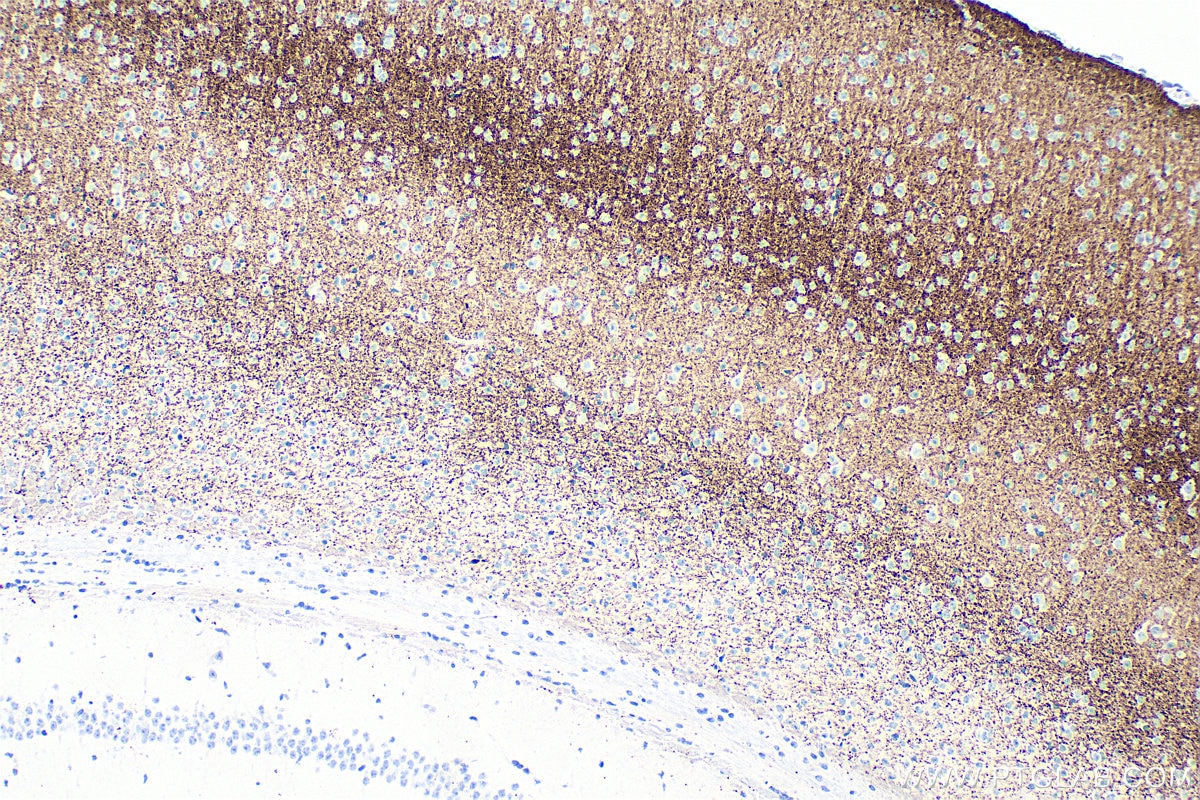

| Positive IHC detected in | mouse brain tissue Note: suggested antigen retrieval with TE buffer pH 9.0; (*) Alternatively, antigen retrieval may be performed with citrate buffer pH 6.0 |

| Immunohistochemistry (IHC) | IHC : 1:1000-1:4000 |

84083-2-RR targets VGLUT2 in WB, IHC, IF-Fro, ELISA applications and shows reactivity with human, mouse samples.

VGLUT2, also known as SLC17A6, belongs to the major facilitator superfamily. VGLUT2 is a multifunctional transporter that transports phosphate at the plasma membrane and glutamate in synaptic vesicles (PMID:33440152, 11432869). VGLUT2 is involved in neurotransmitter loading into synaptic vesicles (PMID: 11698620). VGLUT2 is predominantly expressed in adult and fetal brain, with highest expression in the medulla, substantia nigra, subthalamic nucleus, and thalamus, and low levels in the cerebellum and hippocampus (PMID:10820226).